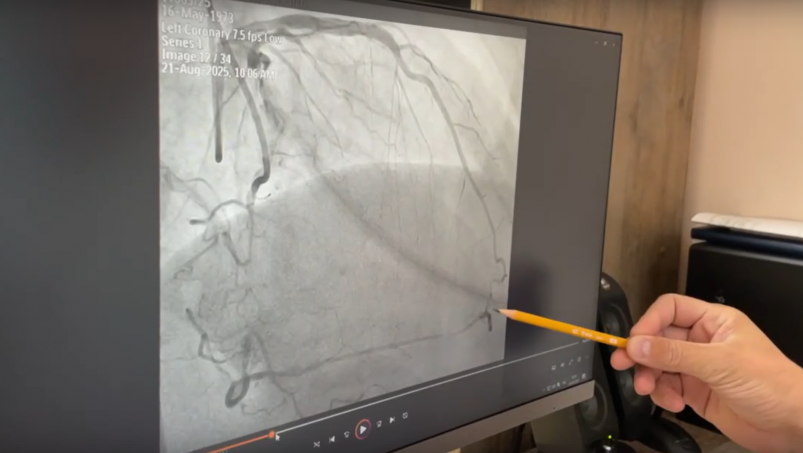

Пациенту с заболеванием сердца провели сложную операцию на сосудах в Ангарске

Ситуация требовала применения самых современных малоинвазивных технологий (ВИДЕО)

В Ангарской городской больнице врачи провели сложную операцию на сосудах сердца пациенту, поступившему с тяжёлым сердечно-сосудистым анамнезом. Ситуация требовала применения самых современных малоинвазивных технологий. Во время хирургического вмешательства применили два доступа — бедренный и лучевой, сообщает ИА AngarskMedia.

Как сообщает в группе ВК (12+) Ангарской горбольницы, во время операции врачи применили сложнейшую технику "tip-in" — соединение разных сосудистых доступов внутри сердца путем введения проводника 0,35 мм в микрокатетер диаметром 0,6 мм. Также восстановили кровоток и имплантировали два стента.

Пациент успешно перенес операцию.

Операцию провела команда отделения рентгенэндоваскулярных методов диагностики и лечения: заведующий Семён Викторович Назаров, врач-хирург Ашуралиев Тохиржон Уктамжонович, операционная медсестра Жанна Геннадьевна Земскова, анестезиолог Лев Геннадьевич Борголов и анестезиологическая медсестра Яна Юрьевна Хитрых.

"Это была действительно непростая операция. Нам пришлось сочетать сразу несколько технологий, но результат превзошёл ожидания — удалось полностью восстановить кровоток", — отметил заведующий Семён Назаров.